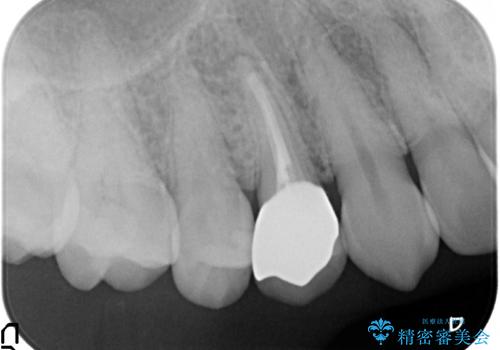

- 右上の歯茎の腫れが引かないので診て欲しいといらっしゃった方の症例です。

検査の結果、右上4番目の歯は神経が死んでおり、そのせいで歯茎に膿の出口が出来ていることがわかりました。

右上4は根管治療を行い、オールセラミッククラウンによる補綴を行いました。